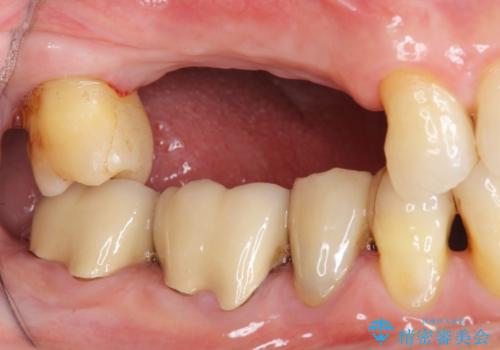

- 右上の奥歯を失ってしまい、「全然モノが噛めない、しっかりと噛めるようになりたい。」

、と入れ歯ではなくインプラント治療を希望され来院されました。

3本の歯が失われた状態を、2本のインプラントで支えるブリッジでの咬合機能回復を計画します。